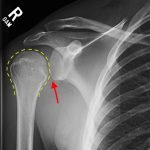

Radiographs demonstrated posterior displacement of the humeral head on the “Y” view (see white arrow) and widening of the glenohumeral joint space on anterior-posterior view (see red arrow). The findings were consistent with posterior dislocation and a Hill-Sachs type deformity. Sedation was performed and reduction was attempted using external rotation, traction counter-traction. An immediate “pop” was felt during the procedure. Post-procedure radiographs revealed a persistent posterior subluxation with interlocking at posterior glenoid. CT revealed posterior dislocation with acute depressed impaction deformity medial to the biceps groove with the humeral head perched on the posterior glenoid, interlocked at reverse Hill-Sachs deformity (see blue arrow).